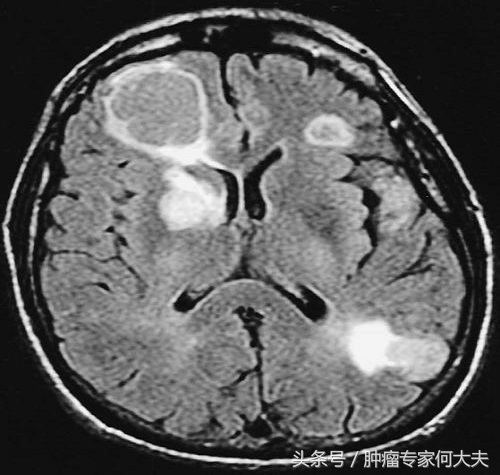

脑转移

2016年4月老太太全身骨痛加重,并出现间歇性意识不清,并有晕厥现象,颅脑磁共振检查提示“多发脑转移”,在家属积极配合下,行全脑放疗10次,放疗后患者一度不吃不喝,消瘦明显,给予最佳支持疗法。患者体能逐渐恢复。治疗上改予“色瑞替尼”(国内暂没有,针对克唑替尼耐药后的替代品),尽管这药很贵,每月自费费用在五万左右,但家属对老人百般孝顺, 不离不弃,定期从外买药给老太太口服。服色瑞替尼的第一个月,老太太肠胃反应很大,反复恶心呕吐,严重腹泻,常出现严重低钾血症、低钙血症,后在中医中药的调解下逐渐耐受了,坚持口服该药1个多月后,老太太意识、精神状况明显好转,多项异常血液肿瘤标记物也明显下降。